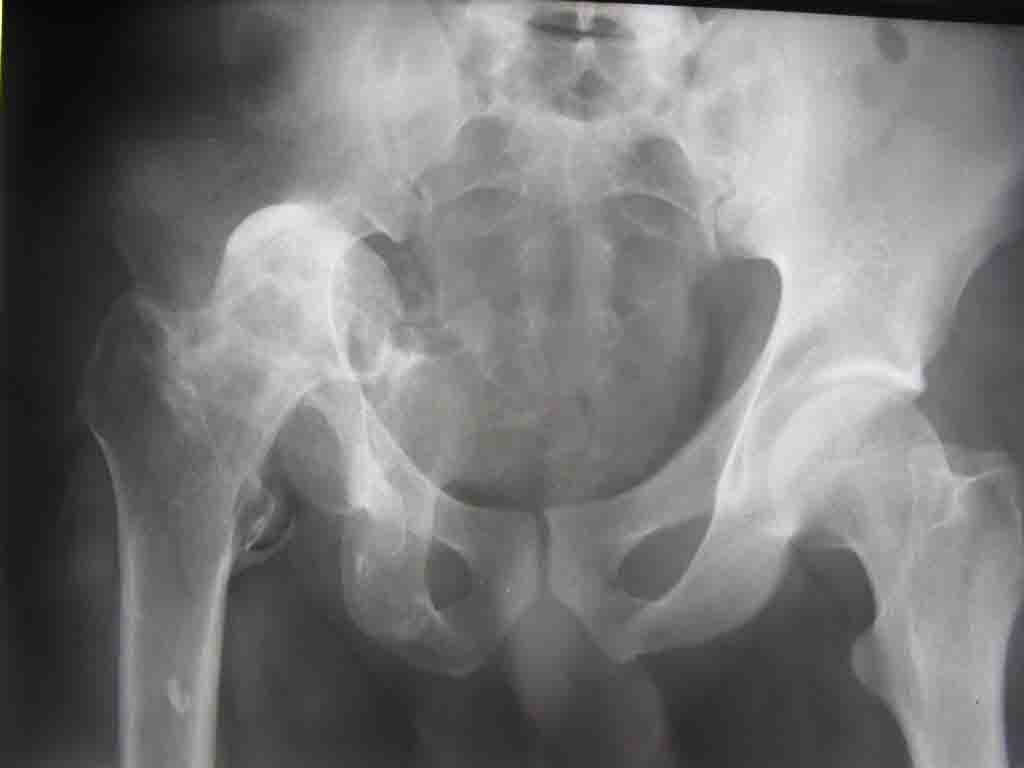

Уважаемые коллеги! На консультацию пришел молодой человек 23 лет с застарелым задним вывихомбедра. После травмы прошло 2,5 ГОДА.

Были переломы бедра и голени на этой же стороне, которые благополучно срослись после остеосинтеза. вывих бедра был пропущен. В настоящее время ходит без дополнительной опоры, есстественно, сильно хромает, выражен болевой синдром, парез седалищного нерва. Сформировался неоартроз в подвздошной области, виден неправильно сросшийся перелом задней колонны, сгибание в суставе до 80.